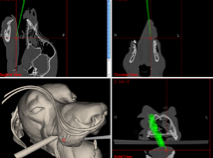

Ansicht der Instrumente in den CT-MRT Bildern

Die Darstellung des Instruments findet in den drei Hauptansichten der Bilddaten sowie im im 3D-Modell statt.